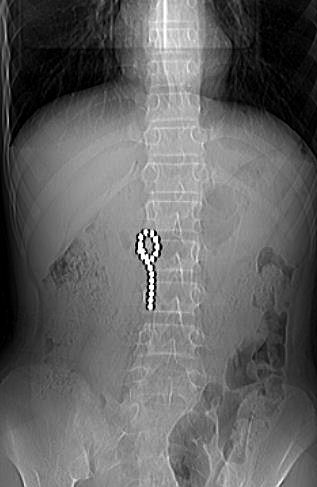

起初,面对医生的询问,小明不敢坦白。结果CT检查下,孩子肚子里清清楚楚得有18颗珠子,已经粘连成串,仿佛吞了一串“珍珠”。

“CT检查不排除珠子重叠的可能,患者腹内至少有18颗以上珠子”,接诊的普外科二主治医师周方建回忆,孩子当时已出现胃壁穿孔及腹腔积液,必须紧急手术。

术中,通过微创腹腔镜探查,医生在患者胃内陆续探查到20颗磁力珠。